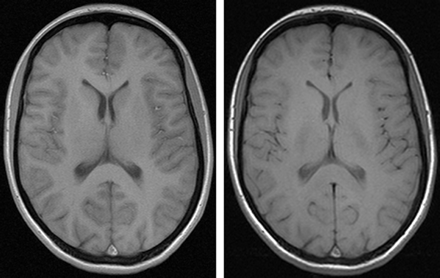

Apparently, gray-to-white matter contrast is reduced in spin-echo T1 imaging at 3T (30) when compared with 1.5T (Fig 6). There are several factors contributing to this observation. T1 times of gray and white matter lengthen and converge at higher fields (31–33). Moreover, shielding effects induced by eddy currents prevent central parts of the image from being properly excited (16), which results in reduced signal intensity of the basal ganglia region. In addition, magnetization transfer effects are enhanced at higher B0, thus reducing signal intensity and contrast. There are several ways to compensate for these effects. For example, inversion recovery sequences appear very well suited if one is only interested in increasing gray to white matter contrast (Fig 7). The inversion pulse, however, interferes with visualization of contrast enhancement following gadolinium administration. Enhancing lesions may not be visible (Fig 8), because in inversion recovery sequences, unlike conventional T1 spin-echo sequences, the tissue with the shortest T1 does not necessarily exhibit the brightest signal intensity, depending on T1. Therefore, inversion recovery sequences are not quite useful for comparative pre- and postcontrast T1 spin-echo imaging, regardless of B0. A different approach to increase gray-to-white matter contrast during T1-weighted spin-echo imaging at both field strengths is to reduce the excitation flip angle (34). Although this reduces SNR slightly, the gain in gray-to-white matter contrast is obvious and more pronounced at 3T (Fig 9). The effect can be predicted from theoretical calculations (35) by using known T1 and T2 relaxation times of gray and white matter (33) but is empirically larger than the theoretical predictions at 3T, probably because of shielding and magnetization transfer effects (34).

Left, T1 spin-echo image at 1.5T (TR, 600 ms; TE, 14 ms; bandwidth, 90 Hz/pixel; section thickness, 5 mm; matrix, 256 × 192; FOV, 220 × 220 mm2; flip angle, 90°). Right, T1 spin-echo at 3T (TR, 700 ms; TE, 10 ms; section thickness, 5 mm; 19 sections; bandwidth, 200 Hz/pixel; matrix, 256 × 192; FOV, 220 × 220 mm2; flip angle, 90°), which is indicative of the reduced gray-to-white matter contrast at higher fields.